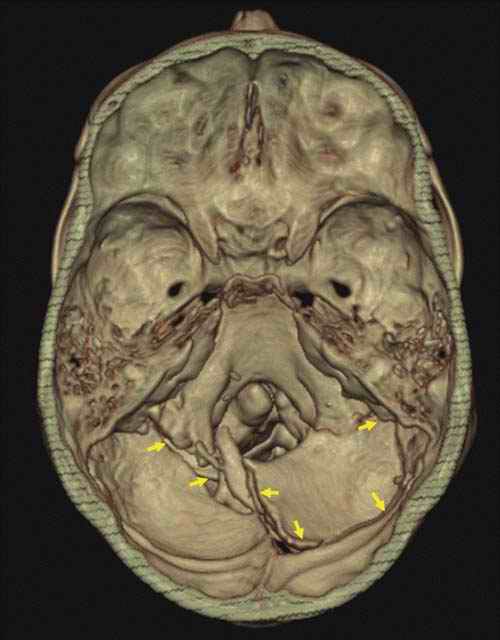

Indirect blunt traumas of the head encompass changes of velocity. The head is relatively heavy. The resulting inertia can lead to various lesions, typically of the skull base. These fractures of the skull base can be of great reconstructive value. If the fractured area is dislocated into the fossa posterior, the lesion must have occurred due to a deceleration of the head toward the spine in a stamp-like manner [12]. Such a constellation is seen in cases from falls from great heights such as suicidal falls onto the feet or in parachute accidents. The opposite is true for a rapid acceleration of the head from the spine. As the skull base is firmly attached to the spine by a multitude of ligaments, traction will result in a tearing of the skull base from the remaining cranium [13]. This rather rare finding is seen in cases such as motorcycle accidents.

The relative weight of the head, together with the additional weight of the helmet, can tear the head from the neck in the case of a frontal collision. Torsion of the calvaria from the skull base (Figure D3.2.14 and Figure D3.2.15) has also been described as a mechanism for skull base ring fractures [14]. Another form of indirect blunt trauma of the head is seen in cases of shaken baby syndrome. This very controversial topic is discussed in Chapter D3.3.